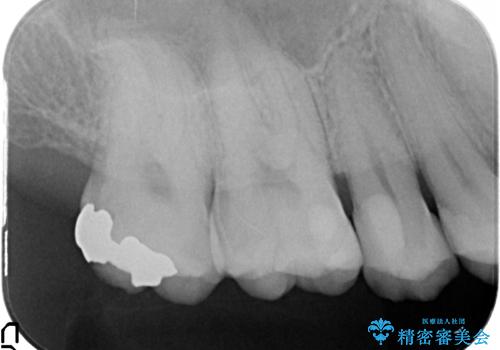

- 以前に治療を行った銀歯がしみることの改善を希望して来院されました。

銀歯辺縁からのセメント漏洩が認められたため、セラミックインレーによる精度の高い修復を行うこととなりました。

辺縁の漏洩について

修復物の精度が悪いと、接着材であるセメントが漏出し痛みが生じることがあります。

劣化の速度が遅い材料を用いて、精度の高い修復を行うことで長期的な予後が期待できます。